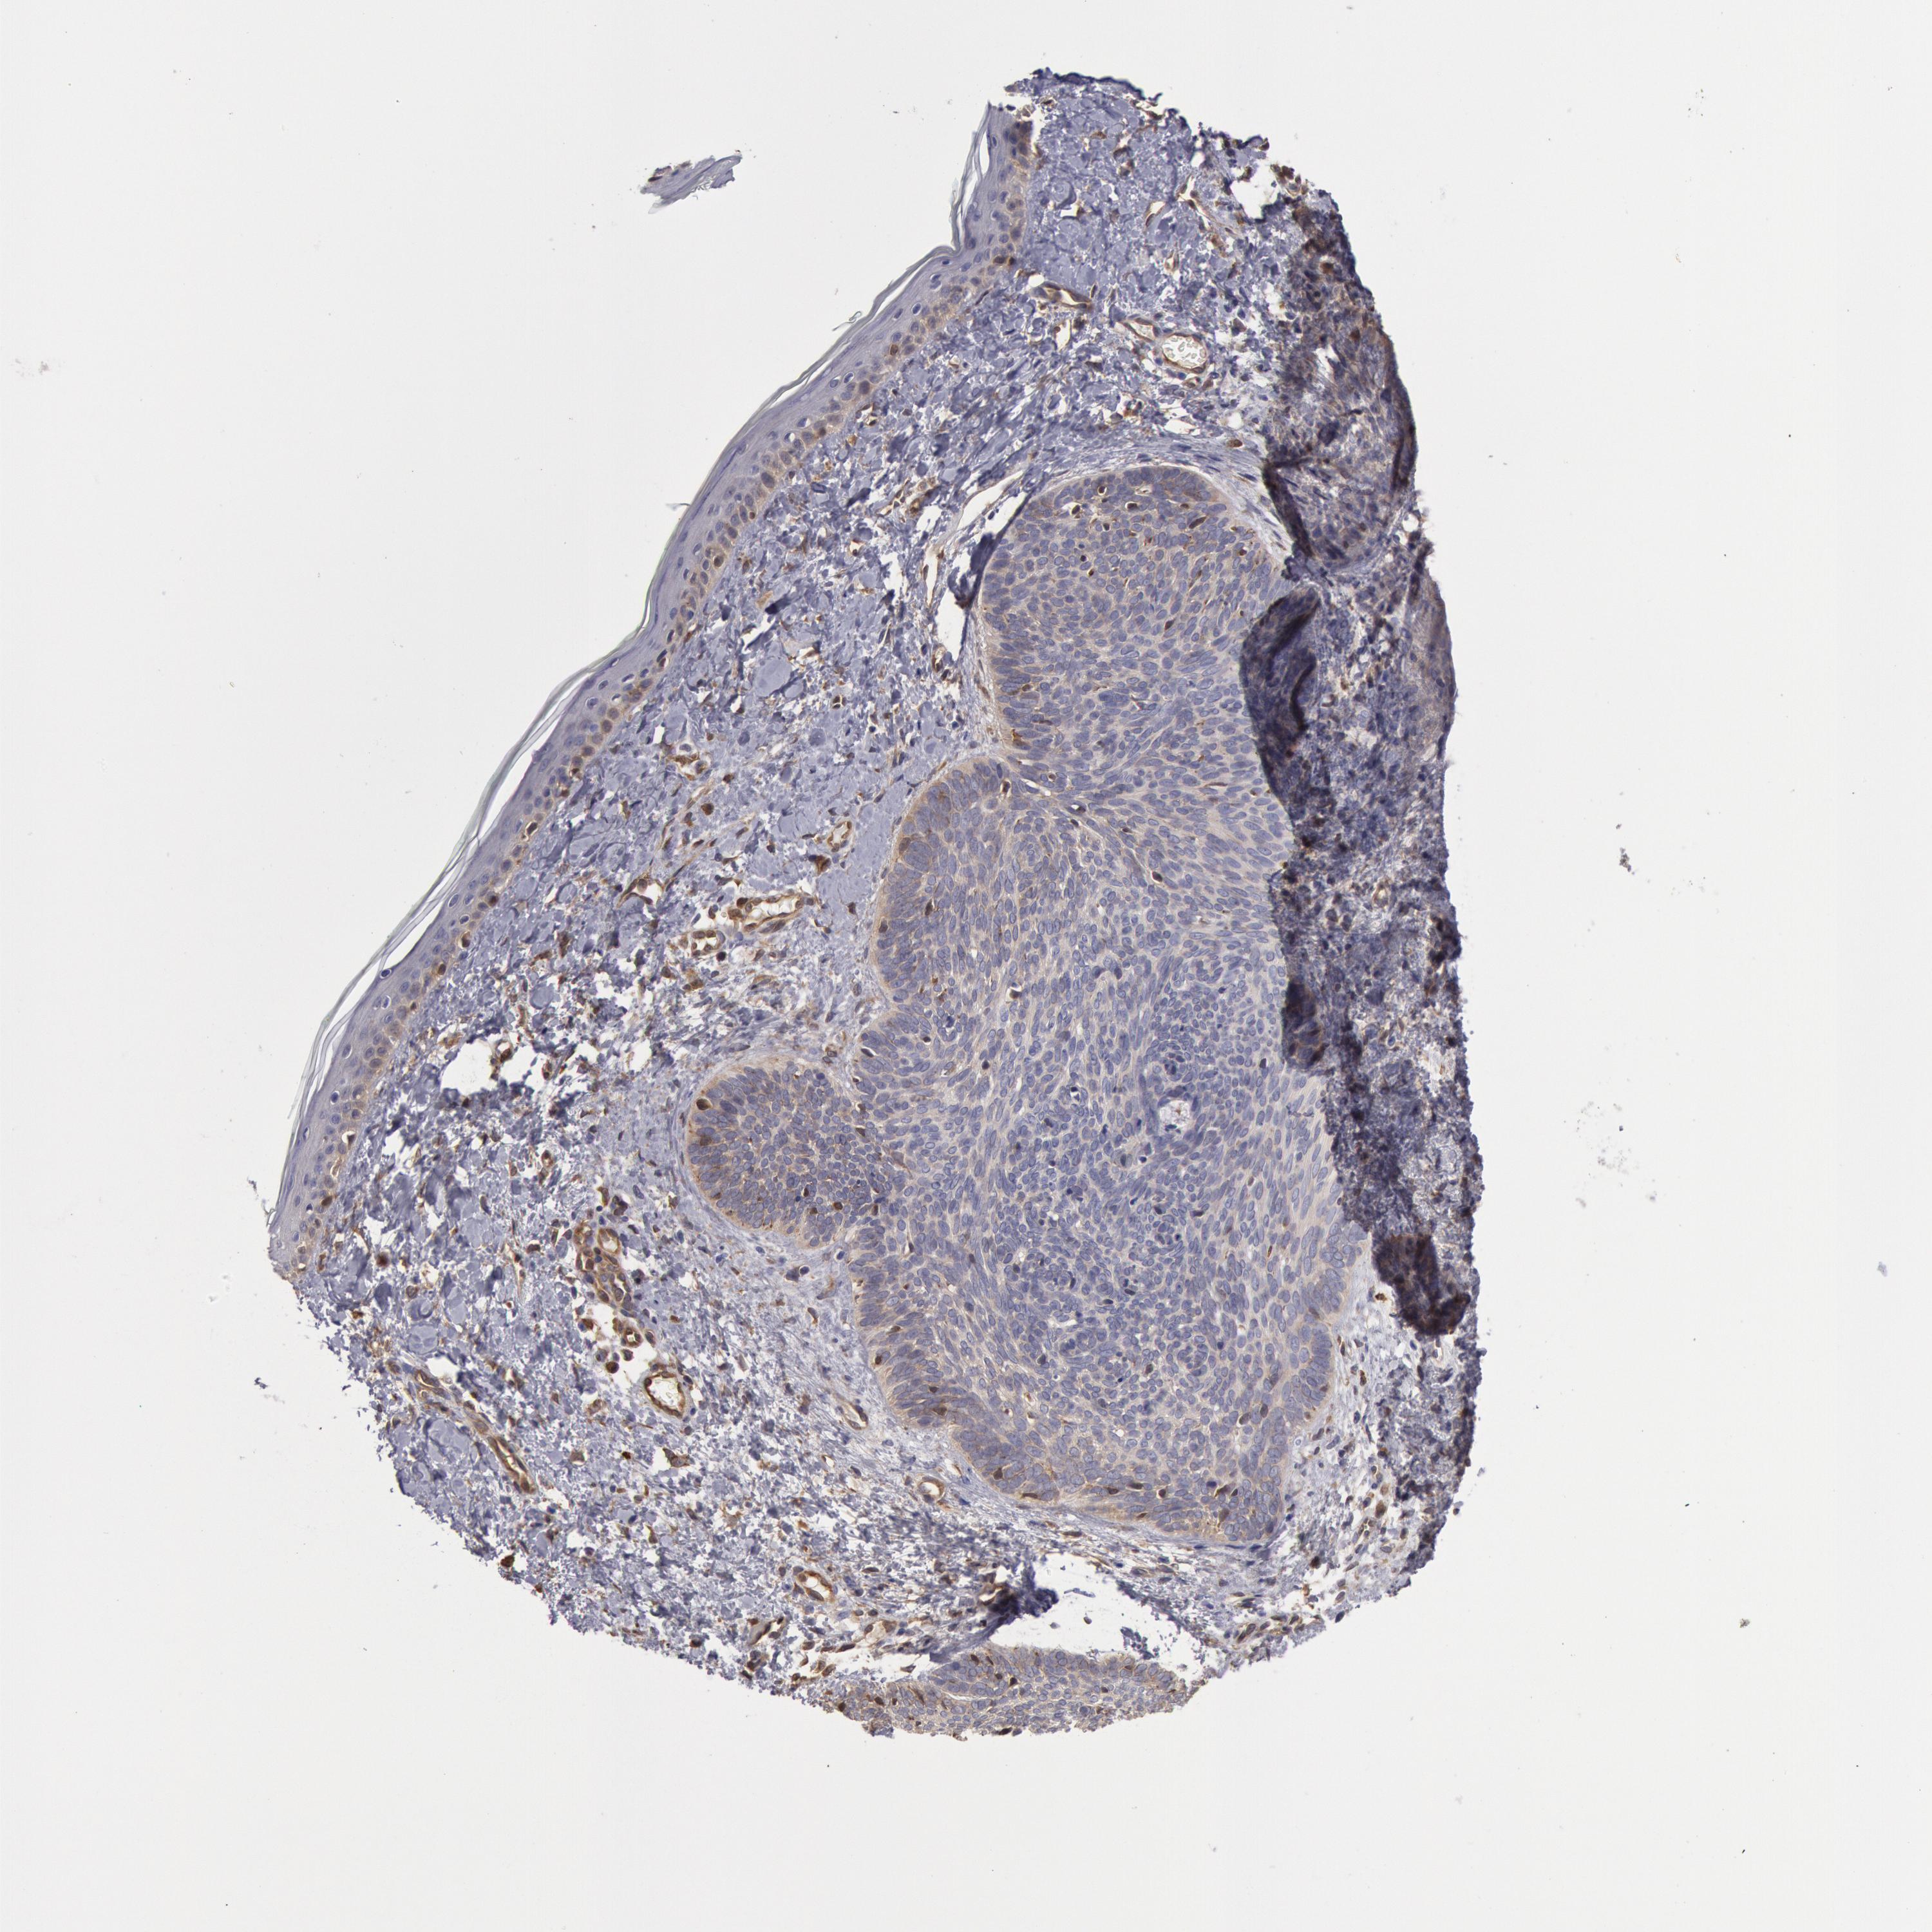

SKIN CANCER - Protein expressioni

A mouse-over function shows sample information and annotation data. Click on an image to view it in a full screen mode. Samples can be filtered based on level of antibody staining by selecting one or several of the following categories: high, medium, low and not detected. The assay and annotation is described here.

Antibody stainingi

Antibody staining in the annotated cell types in the current human tissue is reported as not detected, low, medium, or high, based on conventional immunohistochemistry profiling in selected tissues. This score is based on the combination of the staining intensity and fraction of stained cells.

Each image is clickable and will lead to virtual microscopy that enables deeper exploration of all samples and also displays staining intensity scores, fraction scores and subcellular localization as well as patient and tissue information for each sample.

Antibody HPA001336

Staining

High

Intensity

Strong

Moderate

Weak

Negative

Quantity

>75%

75%-25%

<25%

None

Location

Nuclear

Cytoplasmic/membranous

Cytoplasmic/membranous,nuclear

Squamous cell carcinoma, NOS

Basal cell carcinoma